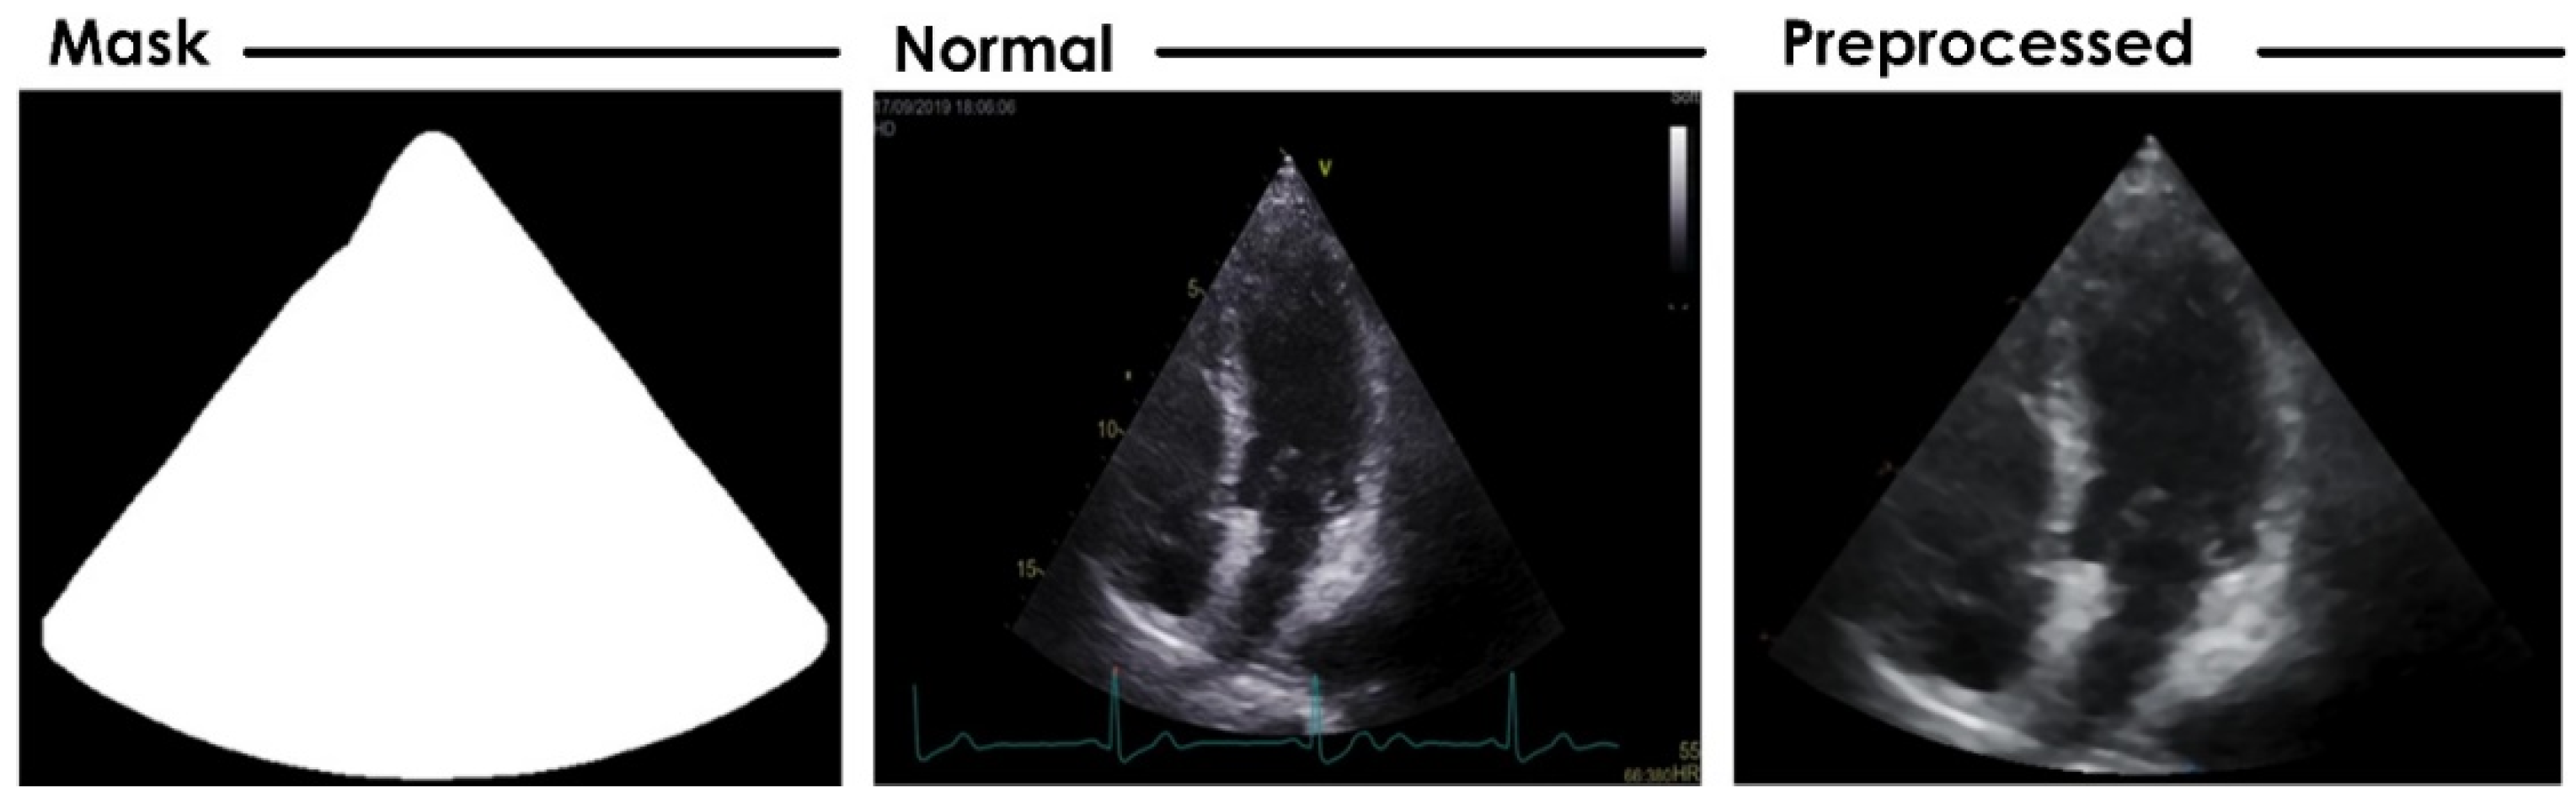

3.1. Preprocessing